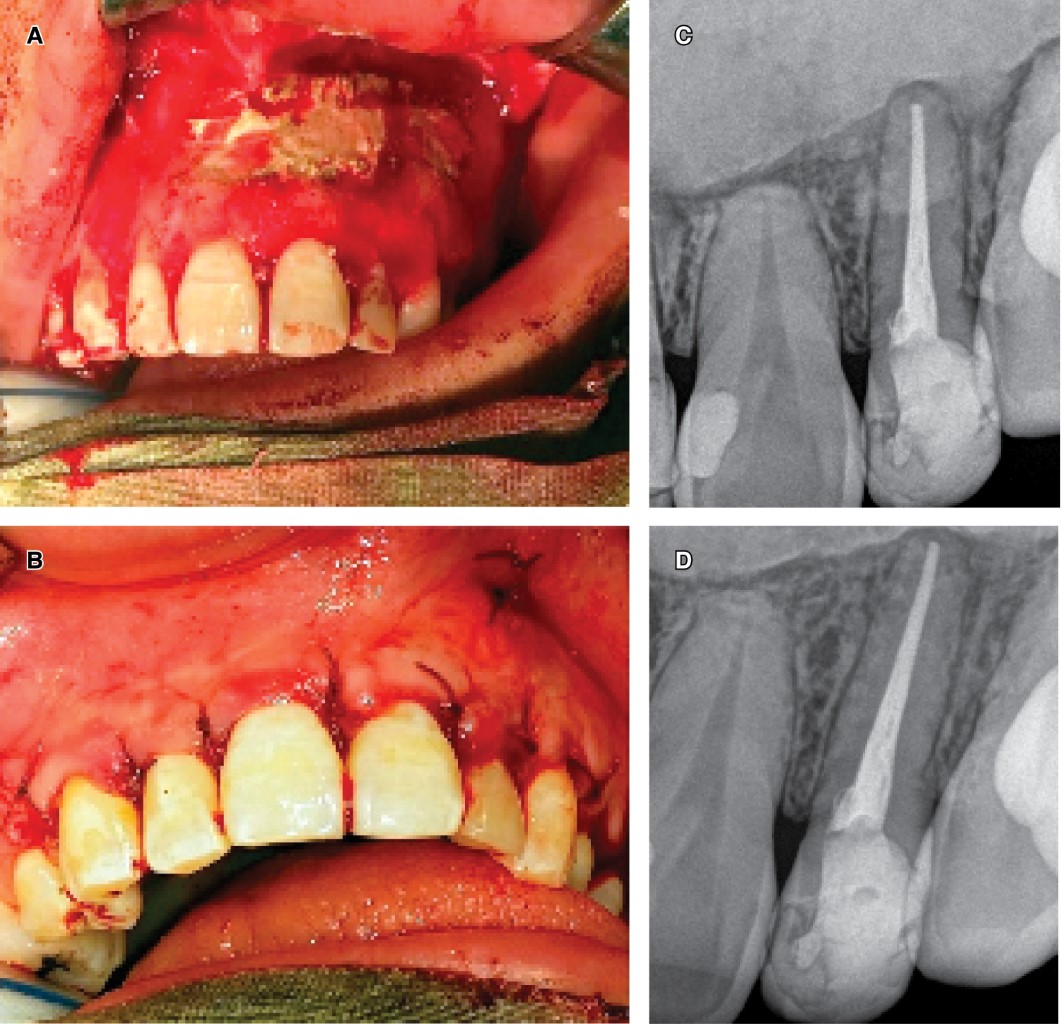

• 1) Treatment of the involved tooth and lesion diagnosis phase: with radiographic and tomographic images, after treatment with antibiotics and having drained the palatal lesion, the root canal treatment of the involved tooth was done, and with rotatory instruments was eliminated the DI, both situations without inconvenience. Due to the endodontic-surgery inter-discipline, endodontic therapy was applied in two sessions, with an intermediate calcium hydroxide-based therapy. An expectant behavior was kept regarding the remaining dental elements compromised with the infectious. An incisional biopsy of the intraosseous lesion was immediately indicated. For this, a mucoperiosteal flap was made from the anterosuperior sector, trepanning, and preserving the vestibular cortex, incising 4 mm from the apex of the compromised tooth. An extensive bone cavity with liquid content was identified, covered by a capsule of difficult enucleation, which was partially extracted for histopathological study. Subsequently, the flap was replaced and sutured together with the placement of a silicone tube for decompressive purposes. The histopathological result revealed a maxillary inflammatory cyst. Figure 3A and 3B show the X-ray image of the drainage through which the patient flushed the cystic cavity. Figure 3C the tissue surrounding the catheter is normal in appearance. This photo was taken four months after initial placement during a device replacement procedure.

• 2) Decompression (conservative treatment phase): placing the drain device to allow washings of the cystic cavity. Initially, the washes were carried out by professionals calibrated for this purpose and later through the instruction to the patient on an outpatient basis. Drain and decompression maneuvers reduced the intracystic pressure generating relief and disappearance of the symptoms. The palatal abscess was remitted. Consequently, root canal treatment of the involved tooth and removal of DI with rotary instrumentation was finished.

• 3) Monitoring and control: monthly clinical and radiographic control was carried out. The patient continued with the washing on an outpatient basis for six months. Bone trabeculae formation and a notable lesion reduction (evident in the intraoral X-ray control) were observed near to the anteroposterior limits of the cystic lesion in the three and 6-month control (Figure 4).